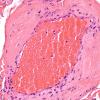

PERIPHERAL NEUROPATHY

11 VASCULITIS - VASCULOPATHY

2 Vasculopathy (2)